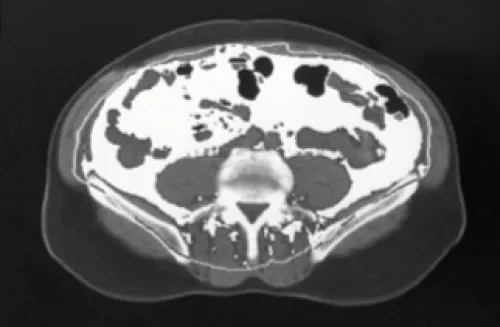

CT scan of abdomen at L4

In PWH, weight gain can occur irrespective of a high BMI and is characterized by the buildup of VAT.2,8

Visceral fat surface area in an actual patient. Surface area above 130 cm2 is indicative of lipohypertrophy.8

Surface area: 155 cm2*